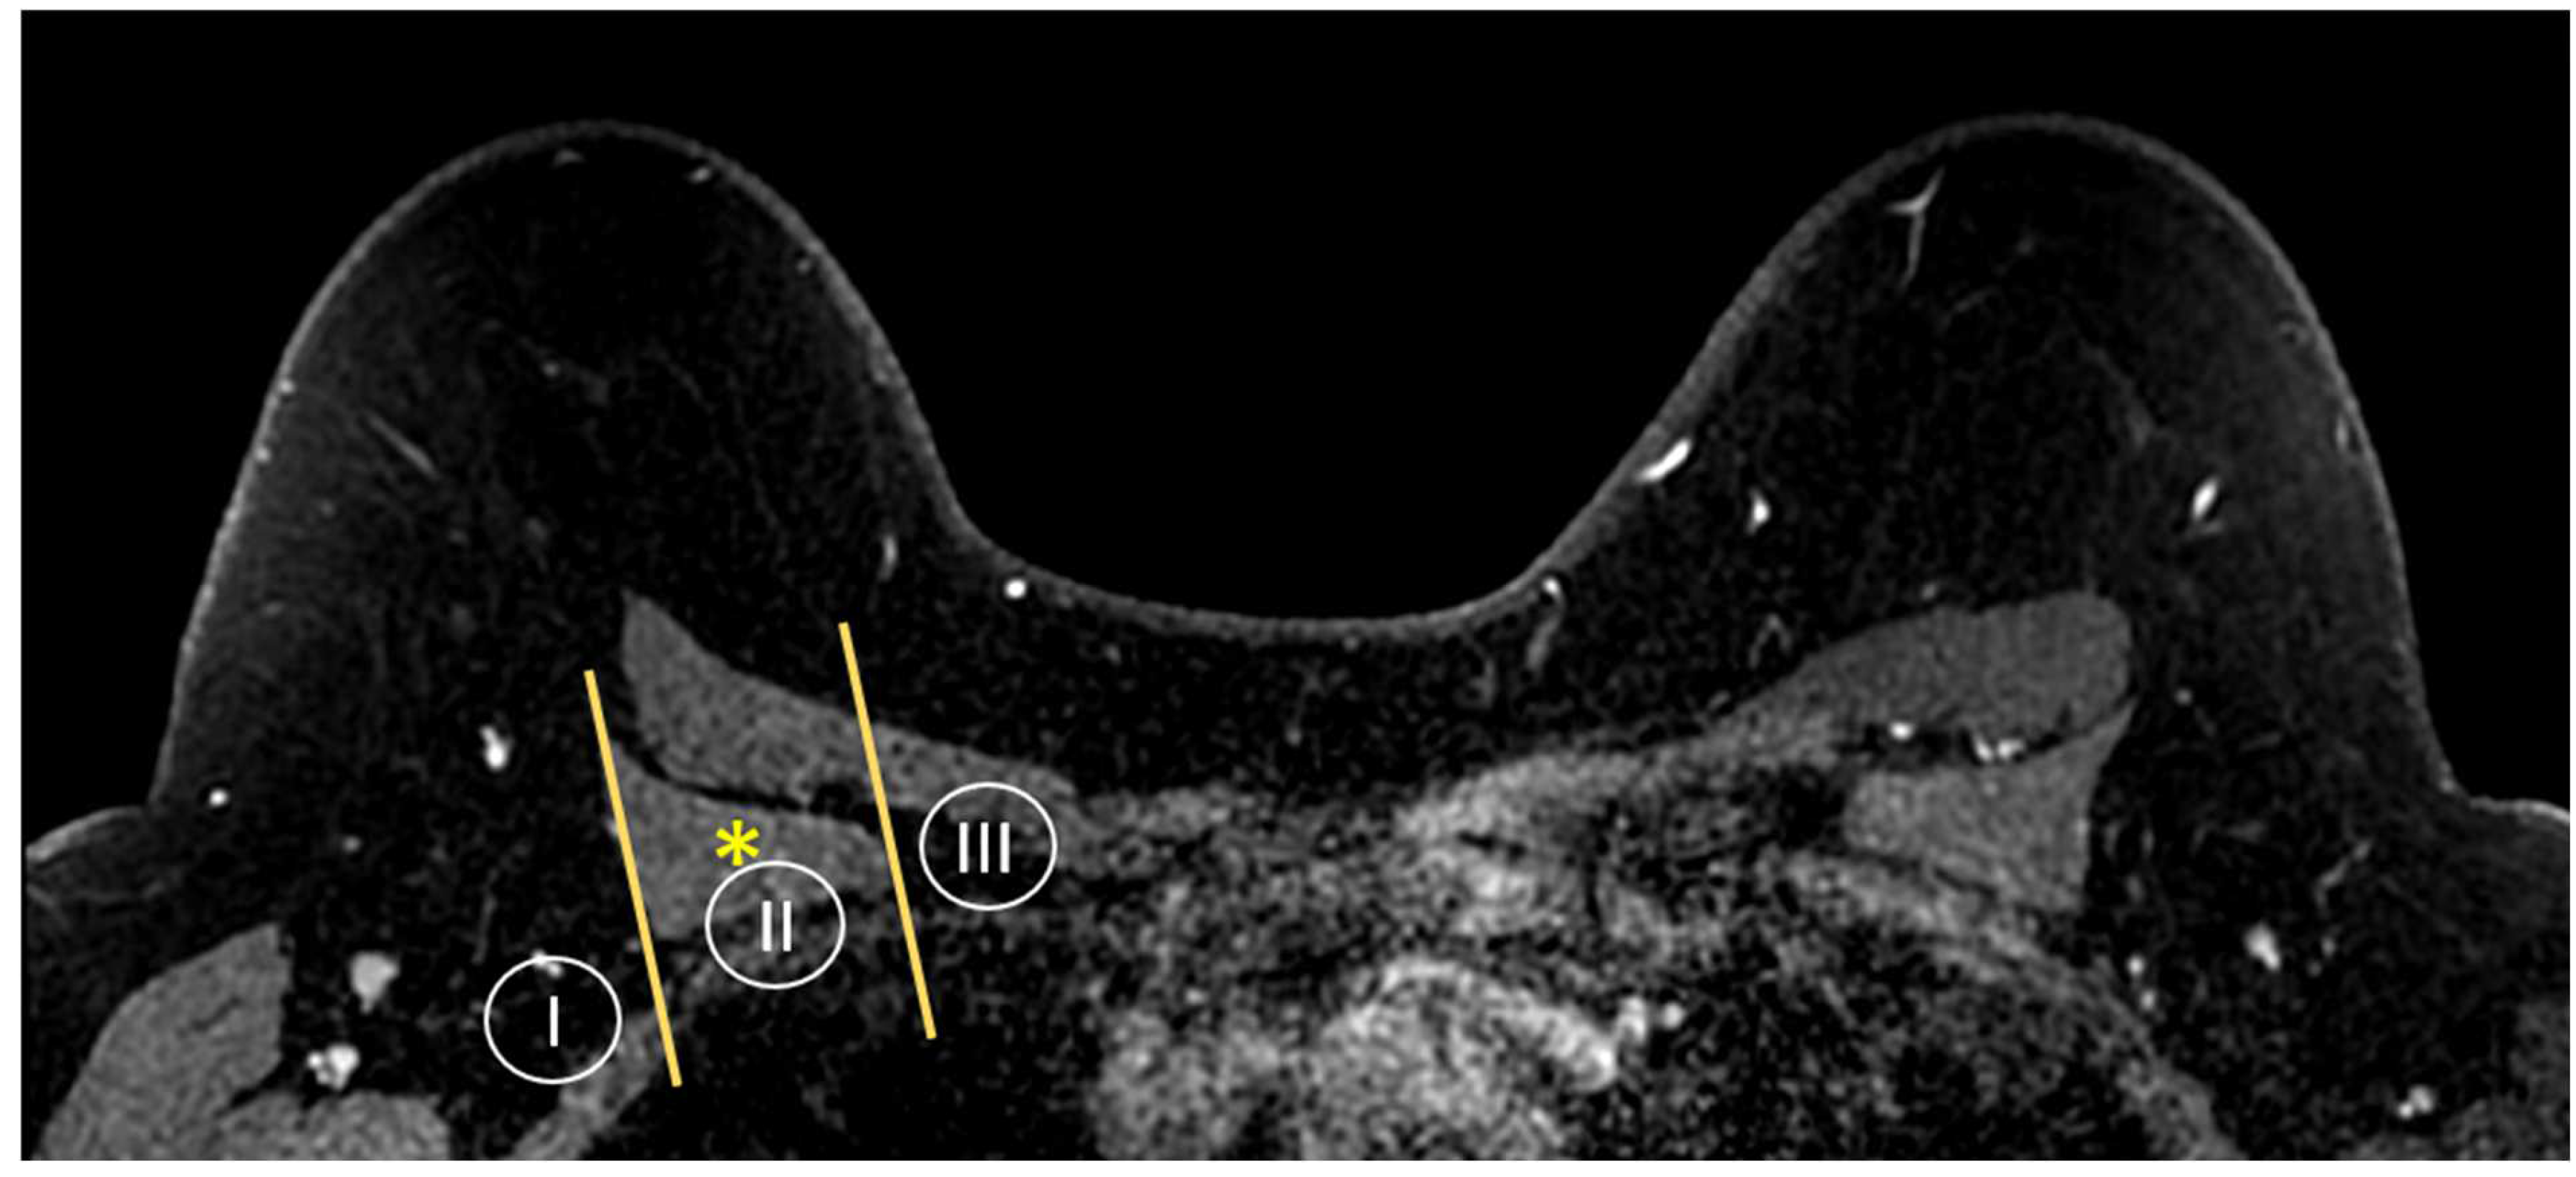

3.1.5. Evaluation of Axillary Lymph Nodes

3.1.6. Evaluation of Internal Mammary Lymph Nodes (IMLNs)